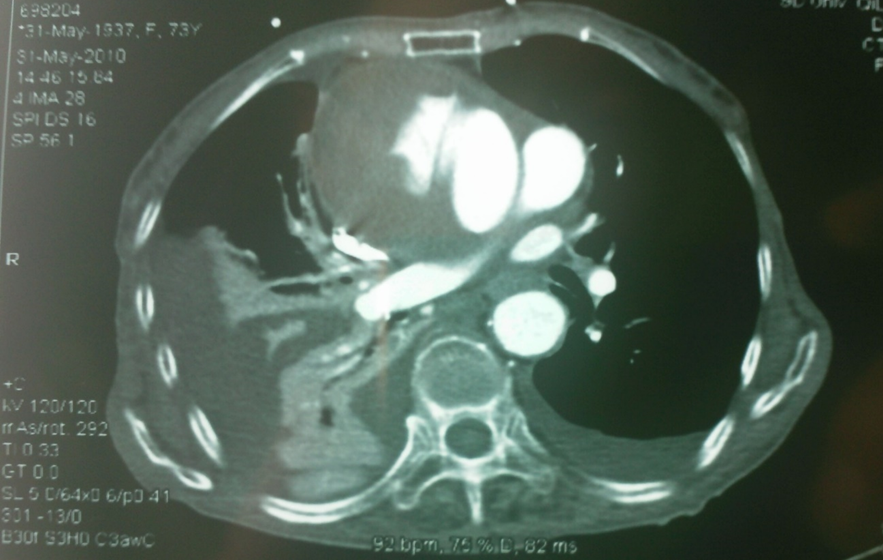

我们早期曾遇到一例升主动脉夹层治疗失败的病例(因失败未留存完整影像),但事后复盘发现,根本原因在于对主动脉三维解剖认知不足。当时采用预开窗技术,支架释放后发生近端移位和远端扭转,导致左颈总动脉与头臂干被遮蔽,最终需紧急补救性支架+两次搭桥手术。

全麻下双上肢穿刺,右股动脉切开,左上肢路径造影,右上肢进保护性导丝,对支架预开窗后植入升主,因破口较大,支架近端掉入破口,远端扭转遮蔽左颈总动脉及头臂干,窗口对破口,再次植入一枚38-80支架,封住近端破口后,以8*60支架开放右侧头臂干,6*10人工血管行右锁骨下-左颈总搭桥,取颈前静脉行左椎动脉-人工血管搭桥,之后造影,头臂动脉均通常,术后约2小时患者清醒。